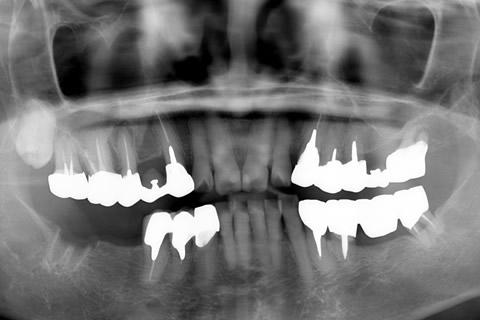

症例2

治療前

インプラント埋入時

治療後

- 年齢・性別

- 57歳男性

- 治療期間

- 3ヶ月

- 抜歯

- なし

- 治療費

- 154万円

- 備考

- 左上5.6.7 及び左下6.7欠損

- 治療内容

- 左上5.6.7と左下6.7欠損部にインプラント埋入

- 施術の副作用(リスク)

- オペによる知覚障害。インプラントによる歯肉炎。インプラント脱落。